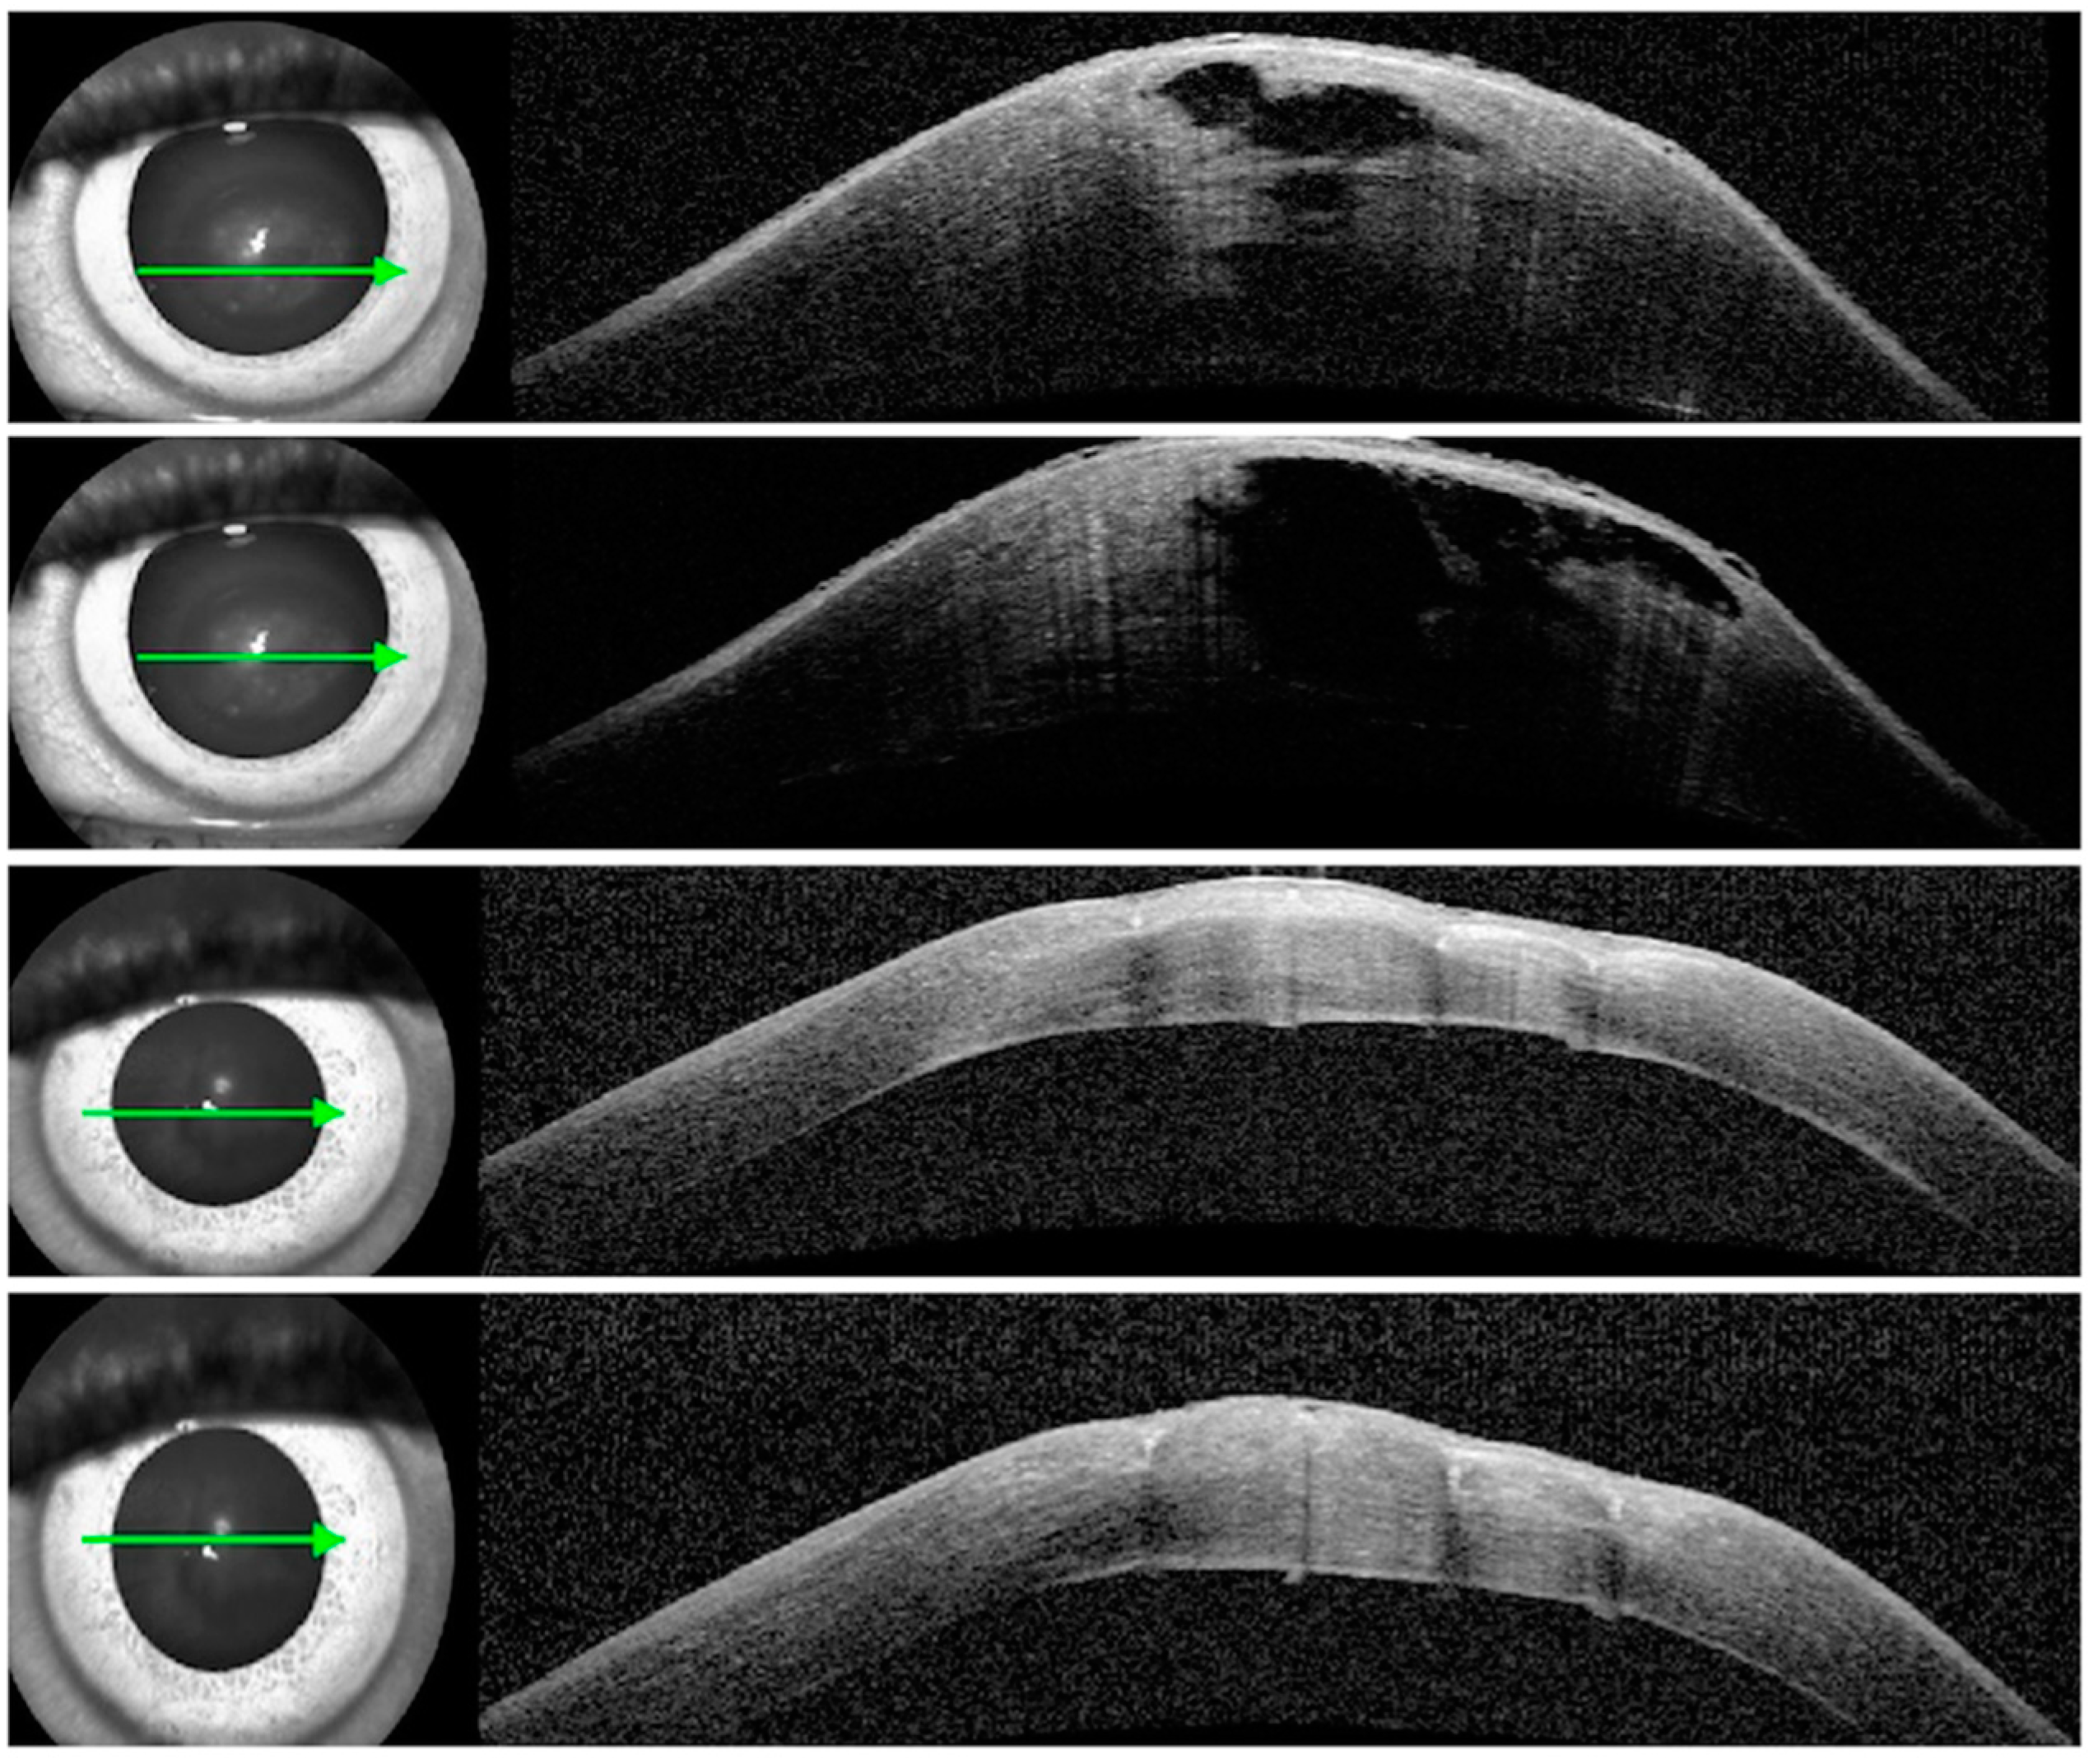

Case 2: A 20-year-old female of Afro-Caribbean origin, diagnosed with keratoconus since the age of 18, presented with acute hydrops in her right eye. Her best spectacle-corrected visual acuity (BSCVA) was hand movement (HM). Her maximum keratometry increased from 83 dioptres (D) to 124D, and her apex pachymetry changed from 340 µ to 1380 µ. ASOCT confirmed the presence of stromal clefts (Figure 3). Conservative management was started, and within one week she received four full-thickness compressive corneal sutures, as described above. There was a complete resolution of her symptoms and corneal oedema in 8 days. The sutures were removed in four weeks. She was not keen on RGPCL. Her final BSCVA improved to 6/36 in the affected eye, one line lower than her pre-hydrops vision of 6/24.

Figure 3. Anterior segment OCT: pre-op with a stromal cleft (top 2 scans) and apex pachymetry of 1380 µ, and 8 days post-op (bottom 2 scans) with apex pachymetry of 548 µ. The arrow shows the level of the scan.